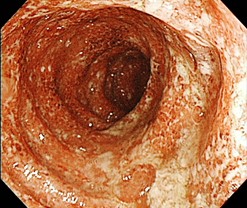

炎症性腸疾患(Inflammatory Bowel Disease; IBD)は潰瘍性大腸炎とクローン病に分類されます。どちらも腸に慢性に炎症が起きる病気で原因がわかっておらず難病に指定されています。日本の患者数は増加傾向で潰瘍性大腸炎22万人、クローン病7万人以上いると推定されています。20~30歳代に発症することが多く就学、就労などへの影響も大きい疾患です。現在当院では潰瘍性大腸炎(UC)の方が約350名、クローン病(CD)の方が約100名、診療を受けています。

CDの治療は内科治療(薬物治療や栄養療法)と外科治療(手術)があります。内科治療が主体となり、薬物治療として、5-ASA製剤が最初の治療選択肢として広く用いられています。また、栄養療法として経腸栄養(刺激が少なく、脂肪分の少ない栄養剤の内服)が行われます。5-ASA製剤や栄養療法にて症状改善ができない場合には副腎皮質ステロイドの投与を検討します。さらに、再燃予防のためには免疫調節薬(アザチオプリン[イムラン®など])も用いられます。これらの治療で十分な効果が得られない場合には、下記のような生物製剤(特定のタンパク質に向けた抗体)の使用が検討されます。